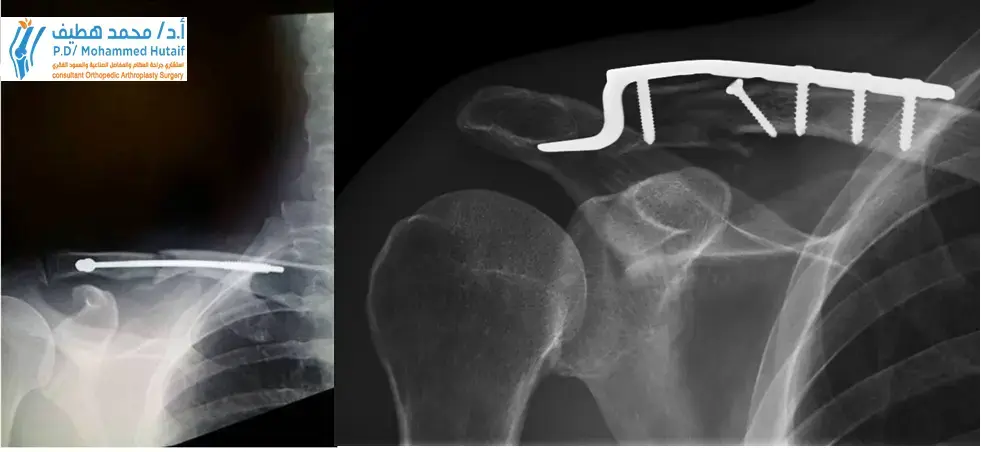

- التثبيت الداخلي بالصفائح والمسامير (Open Reduction and Internal Fixation - ORIF with Plates and Screws): هذه هي الطريقة الأكثر شيوعًا. يقوم الجراح بفتح الجلد، وإعادة العظام المكسورة إلى محاذاتها الصحيحة، ثم تثبيتها بصفائح معدنية ومسامير خاصة. يفضل الأستاذ الدكتور محمد هطيف استخدام هذه الطريقة لما توفره من ثبات ممتاز يسمح بالبدء المبكر في إعادة التأهيل.

- التثبيت بالمسامير النخاعية (Intramedullary Nailing): يتم إدخال مسمار رفيع داخل قناة العظم المكسور لتثبيته. تُستخدم هذه الطريقة في بعض الحالات، خاصةً لكسور الثلث الأوسط، ويمكن أن تكون أقل توغلًا.

- التثبيت (Fixation): بمجرد إعادة محاذاة العظام، يتم تثبيتها بصفائح معدنية خاصة (مصنوعة عادة من التيتانيوم) ومسامير. تتوفر صفائح ذات تصميمات تشريحية حديثة تتناسب تمامًا مع انحناء الترقوة، مما يوفر تثبيتًا قويًا ومستقرًا.